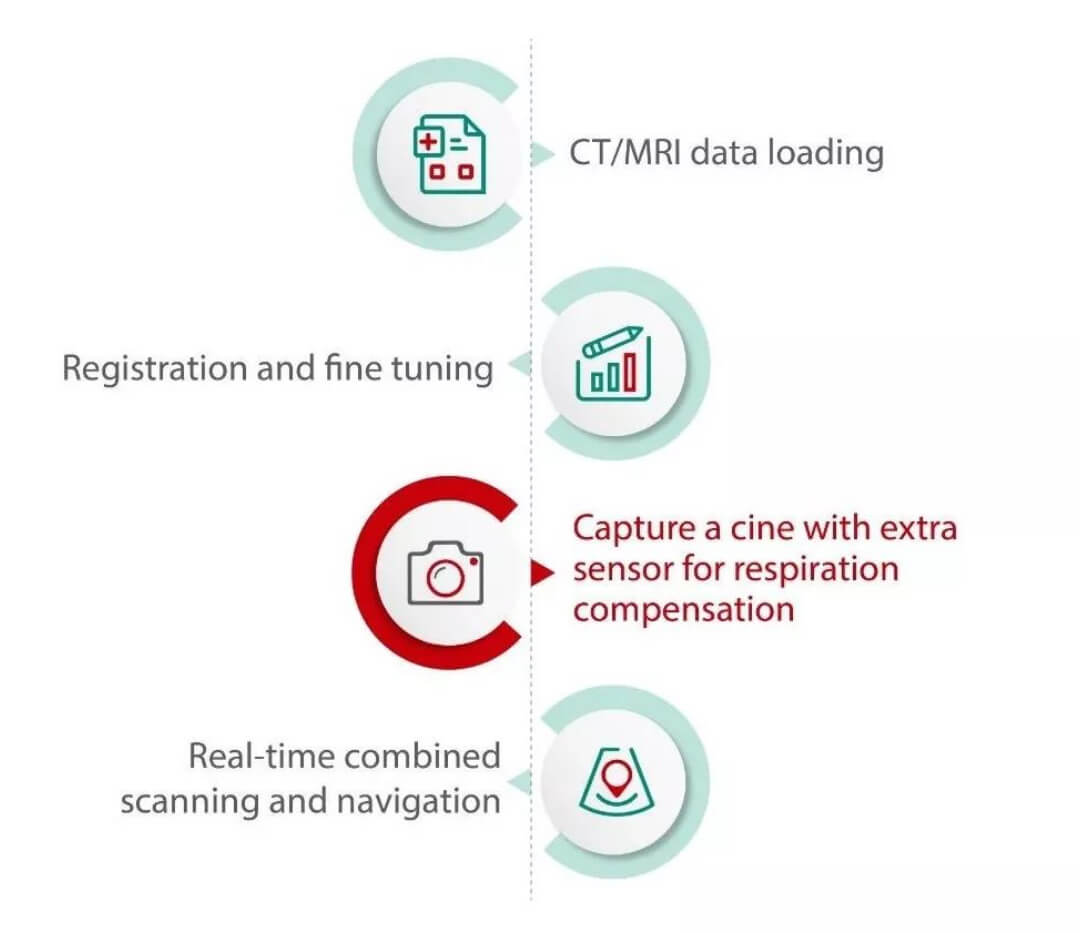

Compared with routine fusion imaging procedure, the new generation iFusion with respiration compensation just needs to add one more step before fusion navigation step.

It has been proved in clinical experiments that Mindray's iFusion can correct approximately 80%[1] of fusion errors caused by respiratory motion and markedly improve the fusion accuracy of a full respiration cycle.